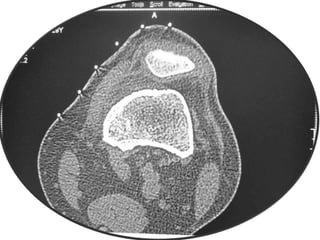

Osteoid Osteoma - CT

• CT is more accurate than MRI.

• CT helped in confirming the diagnosis of

osteoid osteoma in 74% of cases.

• Szendroi et al reported accuracies of about

66% in the diagnosis of intra-articular lesions

and 90% in extra-articular lesions.

• To date, CT scanning is the primary

investigational tool for the definitive diagnosis

of osteoid osteoma.

Osteoid Osteoma -CT • CT is more accurate than MRI. • CT helped in confirming the diagnosis of osteoid osteoma in 74% of cases. • Szendroi et al reported accuracies of about 66% in the diagnosis of intra-articular lesions and 90% in extra-articular lesions. • To date, CT scanning is the primary investigational tool for the definitive diagnosis of osteoid osteoma.